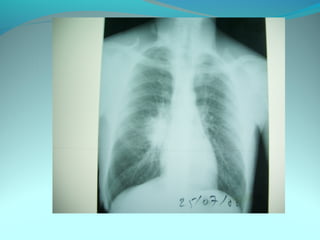

Opacité triangulaire a base cardiaque a sommet

axillaire dense et homogène

Par ailleurs on note

Une opacité plus dense que celle arrondie de 3cm de

diam hilaire gauche ;une surélévation de la coupole

diaphragmatique gauche é poche a aire gastrique

DIAGNOSTIC :

ADP hilaire gauche avec trouble de ventilation

Surelevation de la coupole G et de la poche gastrique

avec de clarté le médiastin

DIAGNOSTIC:

Hernie diaphragmatique paralysie du diaphragme